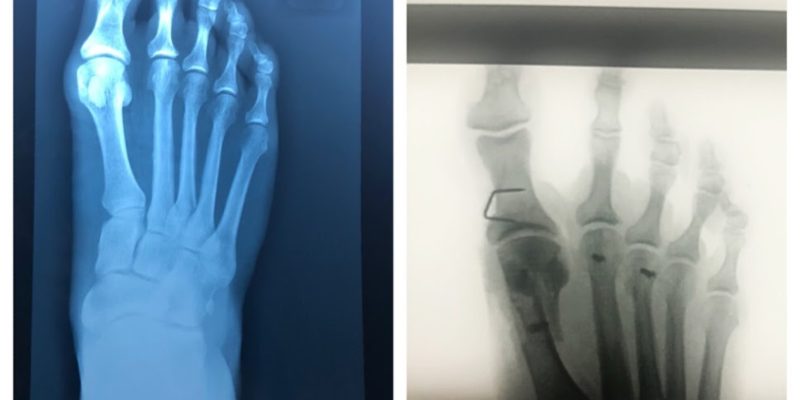

The surgeon found that my 2nd toe had arthritis, caused from that impact injury all those years ago, then exacerbated by the running. He has cleaned out the joint so we hope that this will improve my walking situation markedly. Now with pins in 3 toes and some tendons that have been snipped as there were pulling my toes under too far, I am awaiting the results to see just how successful this surgery has been.

Before and after – dark dots on the image on the right are the screws and staples now permanently embedded in the bones of my foot.